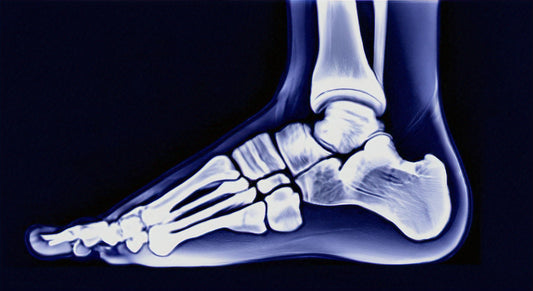

Understanding Plantar FasciitisPlantar fasciitis is a common foot condition that causes pain and discomfort in the heel. It occurs when the plantar fascia, a thick band of tissue that connects...